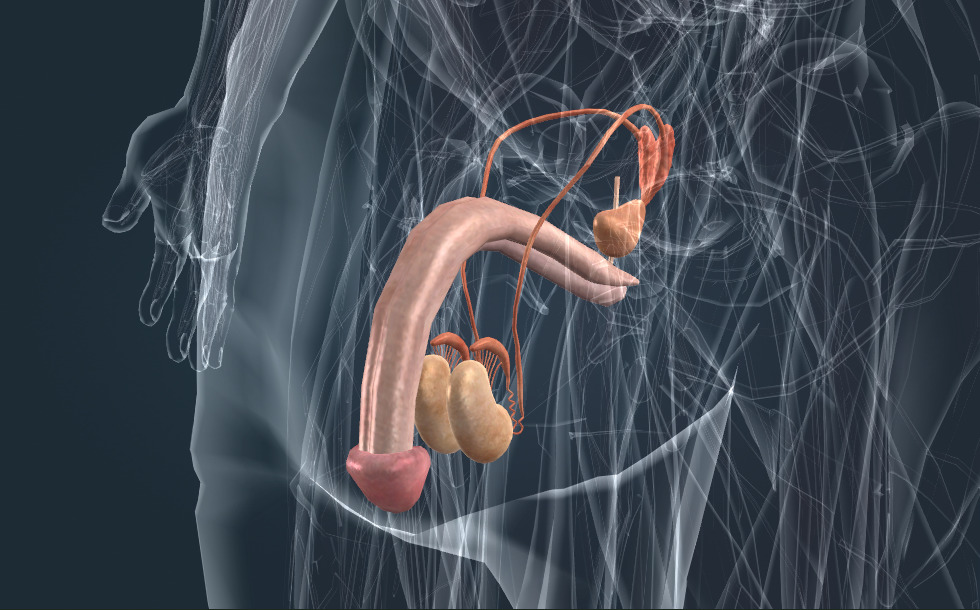

Genitalijos

- sėklidė - Ji gamina sėklą bei tostesteroną (vyrišką hormoną), kuris skatina sėklos subrendimo procesą bei vyriškos figūros vystymąsi ir kūno plaukų augimą.

- kapšelis - Jame saugoma sėklidėse pagaminta sėkla.

- sėklinis latakas

- sėklinės pūslelės - Jos atlieka svarbų vaidmenį sėklos susiformavime.

- prostata - Atlieka svarbų vaidmenį sėklos susiformavime. Taip pat vadinama prostata.

Genitalijos atsakingos už reprodukciją - jos gamina gametas. Apvaisinimo metu kiaušinėlis susijungia su spermatozoidu ir jie suformuoja zigotą, iš kurios ima vystytis embrionas. Sėkla saugoma kapšelyje; ejakuliacijos metu per šlaplę kartu su sėkla išleidžiami spermatozoidai. Sėkla gaminama prostatoje ir sėklinėse pūslelėse.